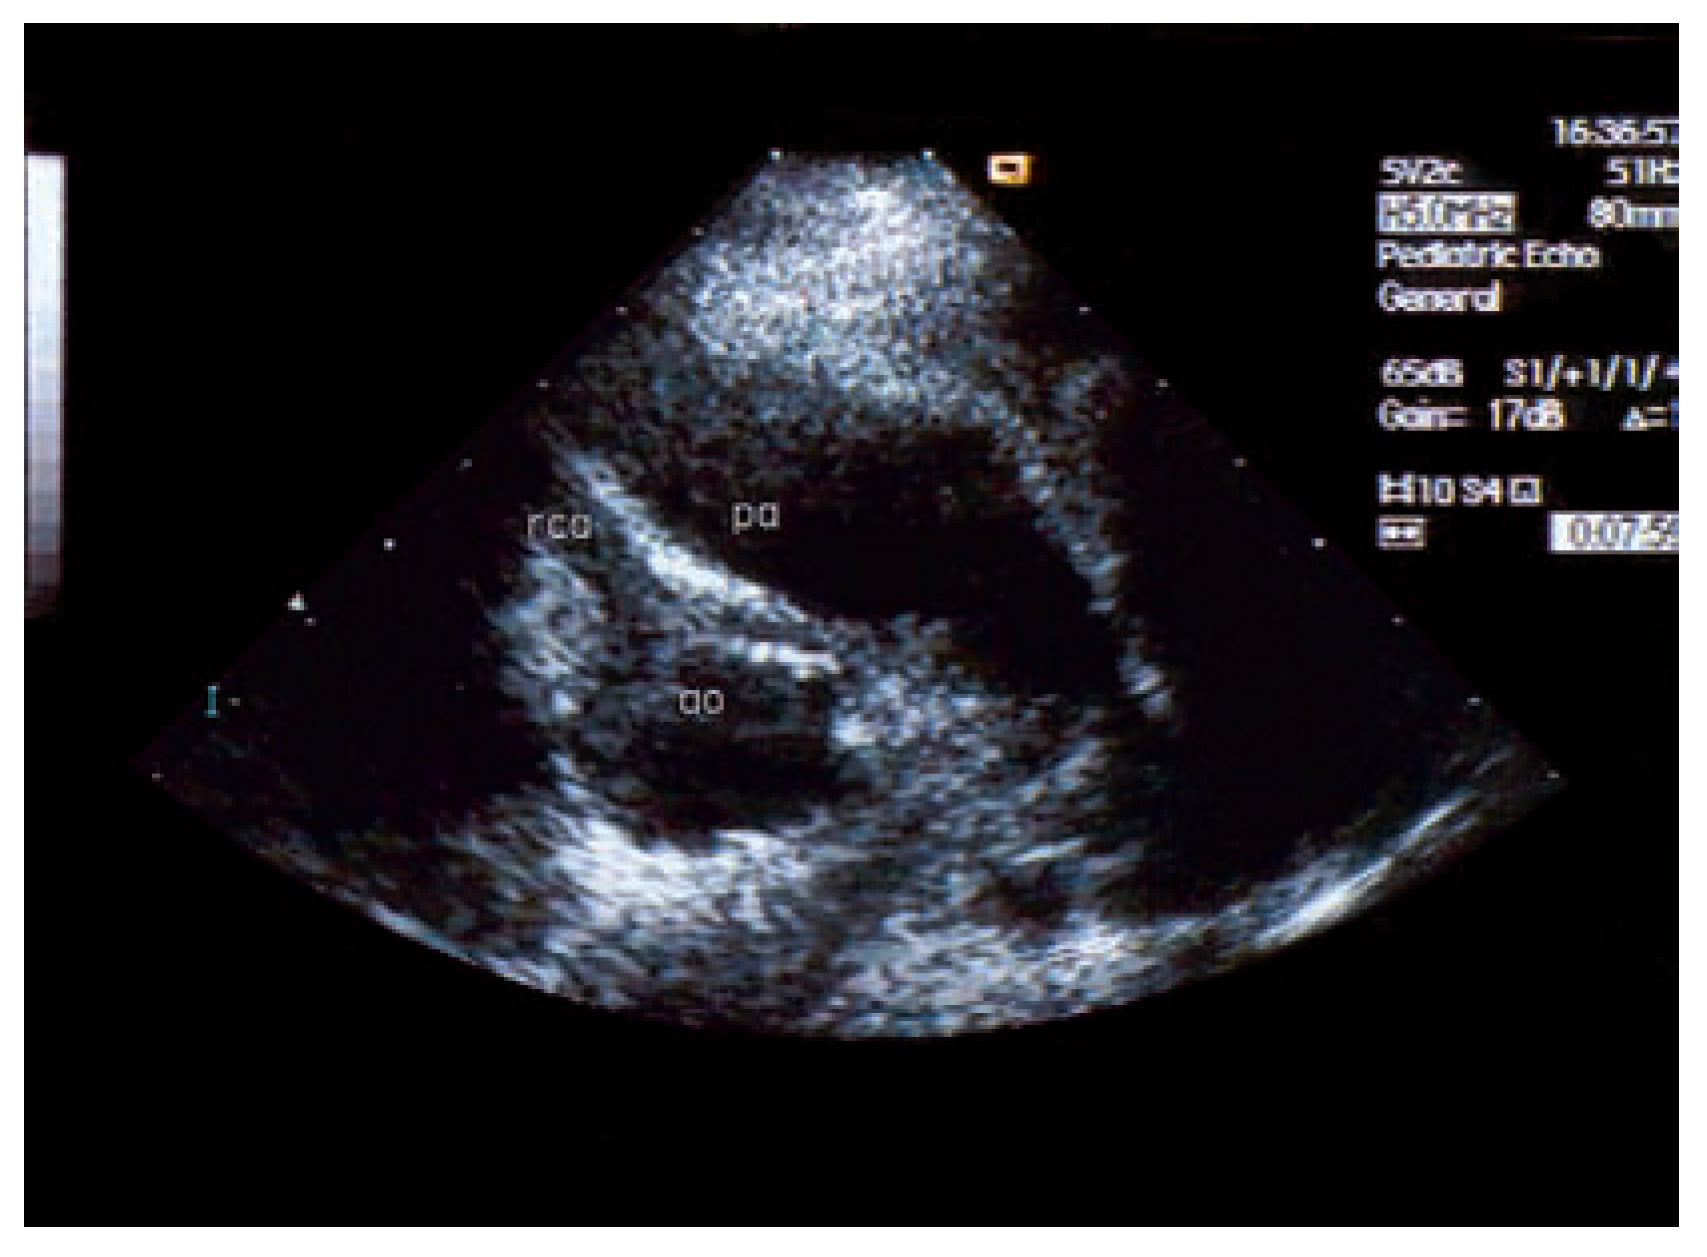

Asymptomatic Bland-White-Garland Syndrome in a 13-Year-Old Girl

Case report